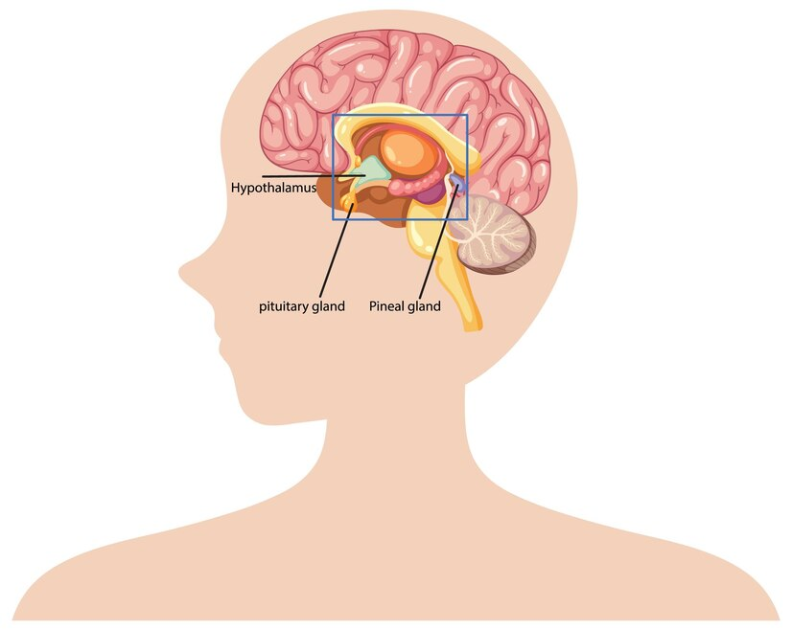

Hipofiz tümörleri, beynin tabanında bulunan ve hormon salgılamadan sorumlu olan hipofiz bezinde gelişen anormal hücre büyümeleridir. Hipofiz tümörlerinin büyük çoğunluğu iyi huyludur (benign) ve metastaz yapmaz. Ancak, hormon üretimini etkileyerek ciddi sağlık sorunlarına yol açabilir.

Hipofiz tümörlerinin teşhisi, detaylı klinik değerlendirme ve görüntüleme yöntemleriyle konur:

- MRG (Manyetik Rezonans Görüntüleme): Hipofiz bezindeki tümörlerin detaylı olarak görüntülenmesini sağlar.